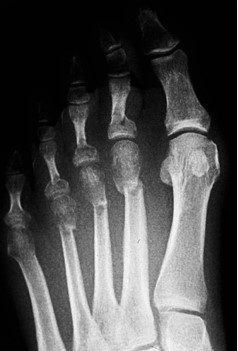

Del estudio radiográfico solo 8 pies cambiaron a Plus (M1>M2), de esos 5 fueron Plus minus (M1=M2) y tres Minus (M1<M2) antes de la cirugía (Figura 5).

En nuestro estudio cambiaron, después de la cirugía DMMO, su fórmula metatarsal ocho pies que eran Plus (M1>M2), 5 se transformaron en Plus minus (M1=M2) y tres en Minus (M1<M2).

Figura 1. Evolución radiográfica de metatarsalgia aislada, radiografía dorso – plantar a) preoperatoria, b) postoperatoria, c) al año de la intervención

Figura 5. Fórmula metatarsal radiográfica global, en ambos grupos, antes y después de la cirugía